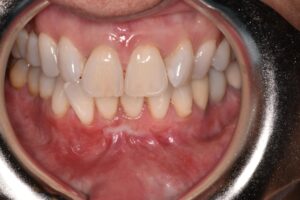

This patient came to us with gum recession, a condition in which the gums pull away from the teeth and expose the roots. Although it may appear to be a cosmetic issue, treating gum recession is medically necessary to prevent root sensitivity, decay, bone loss, and long-term tooth mobility.

Using advanced microsurgical techniques, Dr. Lamas restored healthy gum coverage and rebuilt the protective tissue around the affected teeth. This treatment helps preserve the patient’s oral health, prevent further recession, and maintain long-term comfort and confidence.